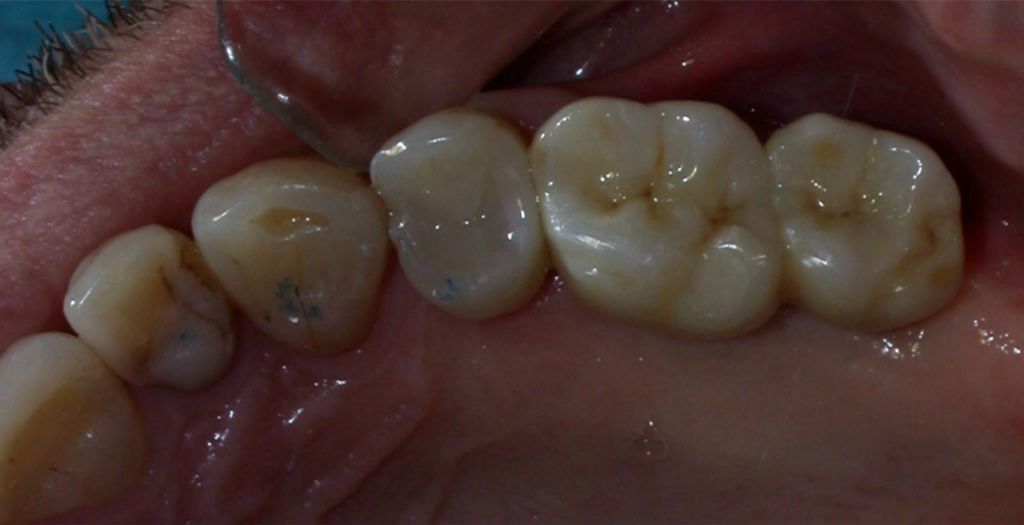

Zirconia bridge on Southern DC Implants